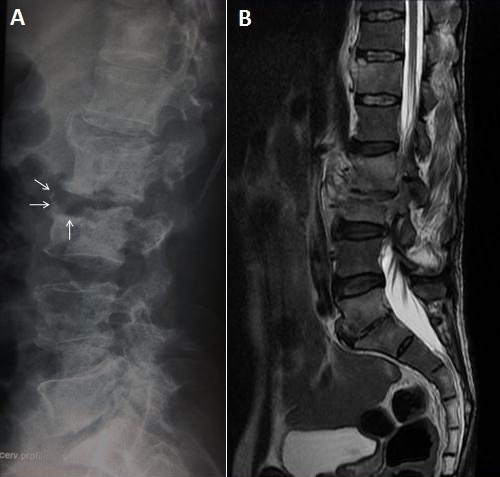

64-year-old man farmar was admitted to our department with low back pain radiating to the lower extremities. He had a history of febrile illness and loss of appetite 2 years before admission. Four months after the start of the febrile illness, the patient started to complain of backache and spinal movements were restricted and painful. He had no other neurologic symptoms. Radiography of the spine revealed parrot's peak appearance (Pedro Pons' sign) at the anterior superior end of the L3 vertebra which is characterized by osteosclerosis and osteophyte (A, arrows). Magnetic resonance imaging (MRI) after the administration of gadolinium revealed L2-L3 epiduritis, an erosive change of the anterior portion of L4 and L5, abnormal signal change with enhancement in T12, L2, L3, L5 and S1 body with probable spondylodiscitis in L2/L3 and L5/S1 levels (B). Pathological analysis of a specimen obtained with CT-guided aspiration revealed non caseating granulomas, which were culture positive for Micrococcus melitensis. Rose Bengal test for brucellosis was positive and Brucella standard tube agglutination confirmed this finding with 1/321 titer. Antibiotic treatment (doxycyline 200 mg/d and rifampicin 600 mg/d) was initiated and the patient's complaints were diminished gradually. He was discharged from hospital and recommended to complete his treatment to 90 days and a follow-up MRI showed sclerosis and reactive osteophyte formation indicating the healing phase of inflammatory tissue at the same levels. Pedro Pons' sign, known as anterior superior end erosion, which occurs together with rounding of the vertebral end and level deformity, is a characteristic radiologic finding of brucellar spondylitis.